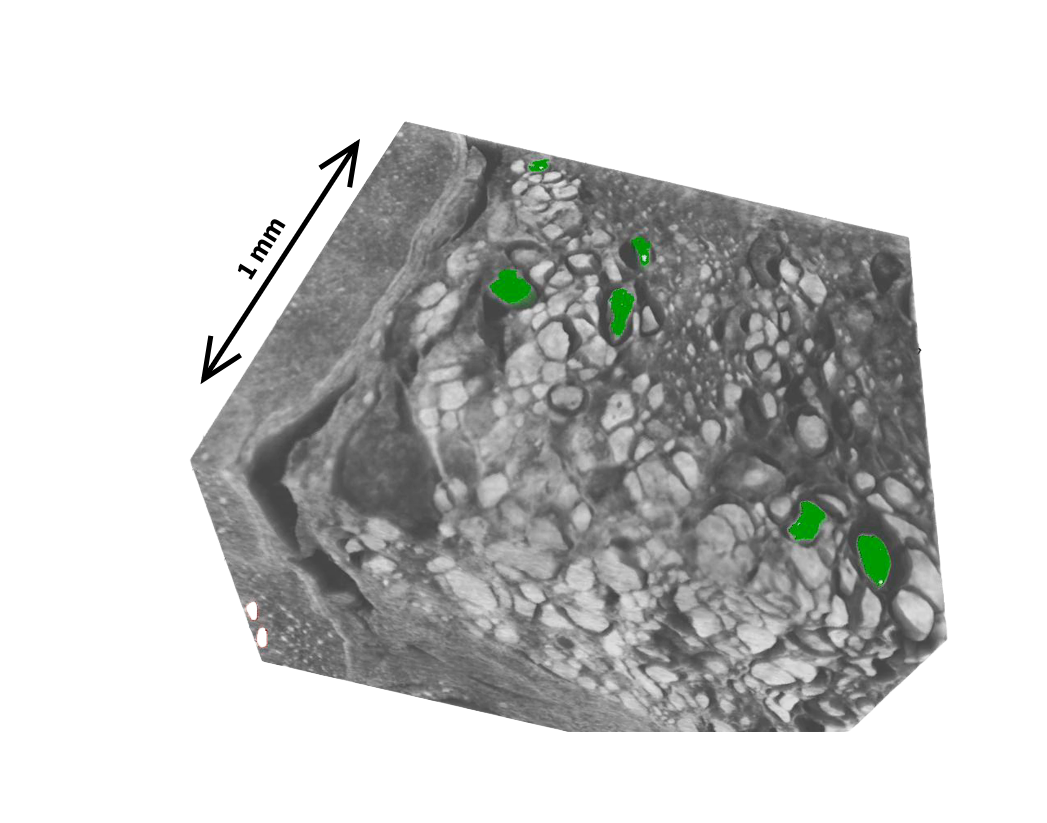

The first part of the project established micro-CT as a practical tool for 3D virtual histology of follicular thyroid carcinomas (FTC). We optimized the scanning protocol for FFPE tissue blocks and validated it on a cohort of 99 FTCs and 31 follicular adenomas. Capsular invasion was clearly detectable, and foci of possible vascular invasion could be flagged for targeted follow-up histology [1].

An ongoing extension of the project is developing a deep learning model that automatically generates spatial attention maps highlighting regions of capsular and vascular invasion in FTCs, removing the need for manual inspection of the full 3D volume.